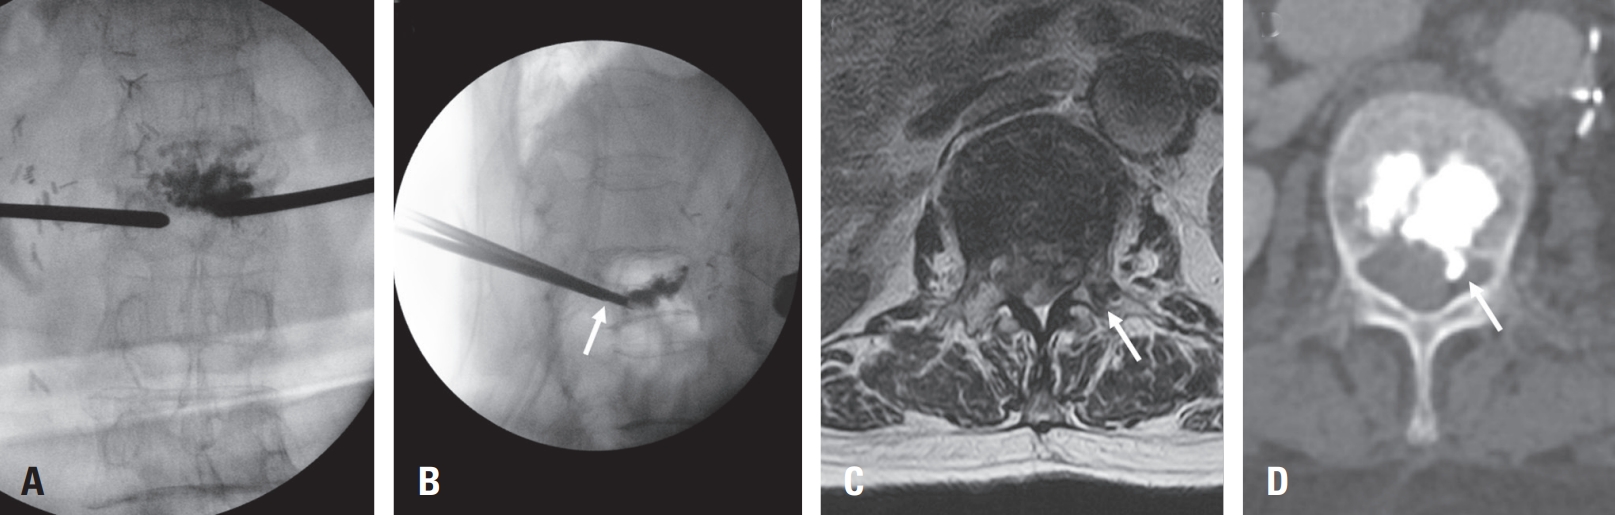

Routine MRI on POD 1 revealed a subdural hematoma at L1–2 and L5–S1 (Fig. 2A), which progressed cranially to the thoracic spine by POD 2 (Fig. 2B). The patient developed new back and buttock pain but remained neurologically intact. Intravenous dexamethasone (4 mg every 6 hours) was administered per spinal cord compression protocol.9)

On POD 4, follow-up MRI showed no further cranial extension of the thoracic subdural hematoma but revealed a new subdural hematoma at the L3–4 level (Fig. 2C). As the patient remained neurologically stable without new symptoms, enoxaparin (50 mg twice daily) was resumed on POD 6, and corticosteroids were gradually tapered.

By POD 11, MRI demonstrated partial resolution of the hematoma with a mixed subdural and epidural appearance (Fig. 2D). Warfarin was reintroduced and gradually resumed at the original dose. The patient was discharged without neurological complications and remained symptom-free at one-month follow-up. This case was conducted in accordance with institutional ethical guidelines and approved by the Institutional Review Board of Eunpyeong St. Mary’s Hospital (IRB No. PC25ZISI0119).

Fig. 2.

Serial postoperative MRI showing the evolution of spinal subdural hematoma. (A) POD 1: Subdural hematomas at L1–2 and L5–S1 levels with thecal sac compression. (B) POD 2: Cranial extension into the thoracic spine with increased spinal cord compression. (C) POD 4: No further thoracic progression, but a new subdural hematoma developed at L3–4. (D) POD 11: Partial resolution of the hematoma with mixed subdural and epidural components.

Fig. 2. Serial postoperative MRI showing the evolution of spinal subdural hematoma. (A) POD 1: Subdural hematomas at L1–2 and L5–S1 levels with thecal sac compression. (B) POD 2: Cranial extension into the thoracic spine with increased spinal cord compression. (C) POD 4: No further thoracic progression, but a new subdural hematoma developed at L3–4. (D) POD 11: Partial resolution of the hematoma with mixed subdural and epidural components.